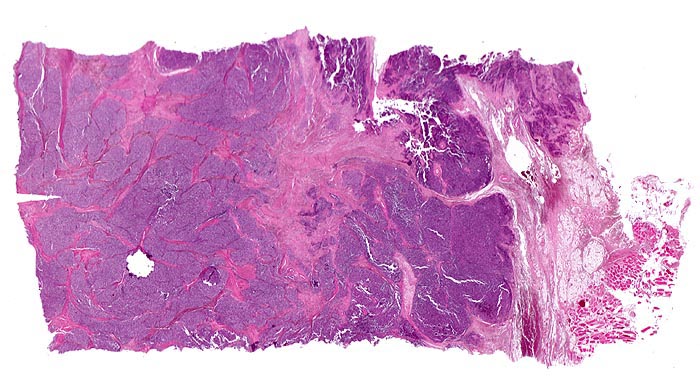

Die Tumoren sind makroskopisch grauweiss und wachsen destruktiv und infiltrativ. Nekrosen und Einblutungen sind häufig. Histologisch lassen sich solide Rasen monomorpher, kleiner, rundlicher Tumorzellen mit dichtem Chromatin und wenig Zytoplasma nachweisen (sog. small-blue-round cells). Metastasen treten vor allem in der Lunge und in anderen Skelettabschnitten auf. Die Differentialdiagnose klein-blau- und rundzelliger Tumoren im Kindesalter ist breit. Kleinzellige Osteosarkome, Neuroblastome, Lymphome und mesenchymale Chondrosarkome können ein histologisch ähnliches Bild zeigen, speziell in kleinen Biopsien, und müssen mit Hilfe von (molekularen) Zusatzuntersuchungen und unter Einbezug klinischer und radiologischer Befunde voneinander abgegrenzt werden.

• Durch Bindegewebssepten abgegrenzte Knoten (lobuläre Architektur).

• Blauer, klein- und rundzelliger Tumor.

• Uniforme Zellen mit schmalem, kaum abgrenzbarem Zytoplasmasaum und unscharfen Zellgrenzen. Rundliche oder ovale Zellkerne mit leicht vergröbertem Chromatin und punktförmigen kleinen Nukleolen.

• Quetschartefakte (gequetschte Zellen sind dunkler und haben verkleinerte abgeflachte Zellkerne).